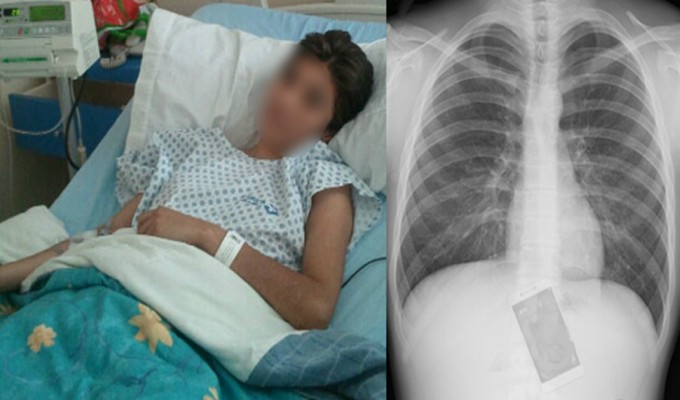

En Brasil, una mujer identificada como Adriana Andrade, de 19 años, fue ingresada en estado de emergencia a un hospital luego de tragarse un celular, para evitar que su pareja leyera algunos mensajes.

La joven fue llevada al hospital donde los médicos pudieron atenderla y ponerla a salvo. Una vez que el celular fue extraído del cuerpo de la chica, el novio pudo revisarlo y constatar por qué la chica tenía tanto afán en esconderlo. Resulta ser que la mujer se estaba escribiendo con su expareja, y tenía planes de reunirse con él esa misma noche sin que su novio lo supiera.